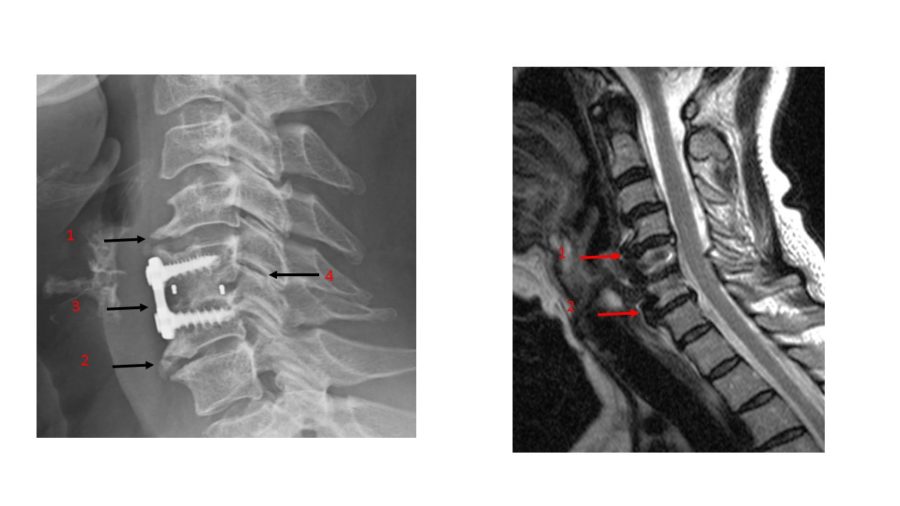

Quy trình Phẫu thuật lấy đĩa đệm và hàn xương cột sống cổ lối trước (ACDF)